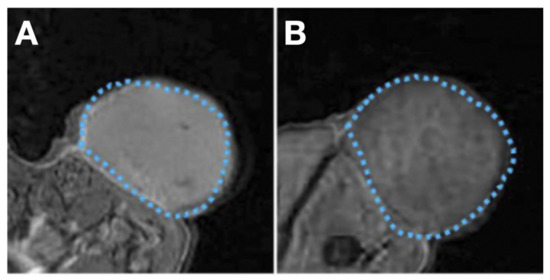

- Rose, F.D.; Braeuer, M.; Braesch-Andersen, S.; Otto, A.M.; Steiger, K.; Reder, S.; Mall, S.; Nekolla, S.; Schwaiger, M.; Weber, W.A.; et al. Galectin-3 Targeting in Thyroid Orthotopic Tumors Opens New Ways to Characterize Thyroid Cancer. J. Nucl. Med. 2019, 60, 770–776. [Google Scholar] [CrossRef]

- Peplau, E.; Rose, F.D.; Eichinger, A.; Reder, S.; Mittelhäuser, M.; Scafetta, G.; Schwaiger, M.; Weber, W.A.; Bartolazzi, A.; D’Alessandria, C.; et al. Effective Rational Humanization of a PASylated Anti-Galectin-3 Fab for the Sensitive PET Imaging of Thyroid Cancer in Vivo. Sci. Rep. 2021, 11, 7358. [Google Scholar] [CrossRef]